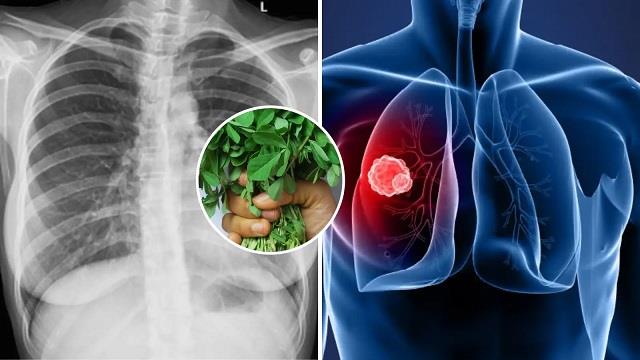

नारी डेस्क: दिल्ली-एनसीआर समेत उत्तर भारत के कई हिस्सों में स्मॉग और वायु प्रदूषण ने हालात बेहद खराब कर दिए हैं। हवा में मौजूद हानिकारक कण (PM2.5 और PM10) लगातार लोगों के फेफड़ों पर हमला कर रहे हैं। इससे अस्थमा, एलर्जी, ब्रॉन्काइटिस और सांस से जुड़ी कई बीमारियां तेजी से बढ़ रही हैं। ऐसे में अपनी डाइट में कुछ खास चीजें शामिल कर फेफड़ों को अंदर से डिटॉक्स करना बेहद जरूरी हो गया है। प्रदूषण के कारण शरीर में ऑक्सीडेटिव स्ट्रेस बढ़ जाता है और इम्युनिटी कमजोर हो जाती है। ऐसे में अगर हम अपने खानपान में ऐसे फूड्स शामिल करें जो विटामिन C, E और ओमेगा-3 फैटी एसिड से भरपूर हों, तो फेफड़ों को प्रदूषण से होने वाले नुकसान से काफी हद तक बचाया जा सकता है।

फेफड़ों को डिटॉक्स करने वाले 5 फूड्स

हरी पत्तेदार सब्जियां और ब्रोकोली

पालक, मेथी, सरसों और ब्रोकोली जैसे फूड्स में एंटीऑक्सीडेंट्स और फोलेट भरपूर मात्रा में होते हैं। ये फेफड़ों की कोशिकाओं को रिपेयर करने और सूजन (Inflammation) को कम करने में मदद करते हैं। इन सब्जियों को डेली डाइट में शामिल करने से सांस लेना आसान हो जाता है।